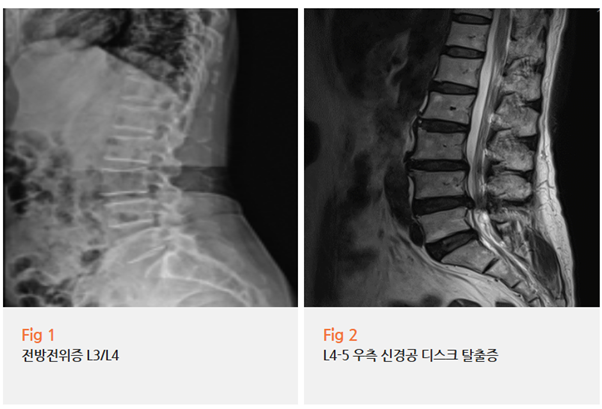

X-ray를 찍어보니...

요추 3-4번에 전방전위증이 보였어요.

하지만 더 ‘정확히’ 확인해야 했기 때문에

환자분께 당일 MRI 검사를 권했죠.

MRI 검사 결과는 더 명확했습니다.

요추 3-4-5번에서 중심부로 심한 신경 협착이 확인됐고,

요추 4-5번 우측에는 디스크 파열까지 있더라고요.

근전도 검사에서도 요추 4,5번에 중증 신경병증 소견이 나왔습니다.

환자분은 꼬리뼈가 아프다고 오셨지만,

정작 문제는 허리 신경이었던 거죠.